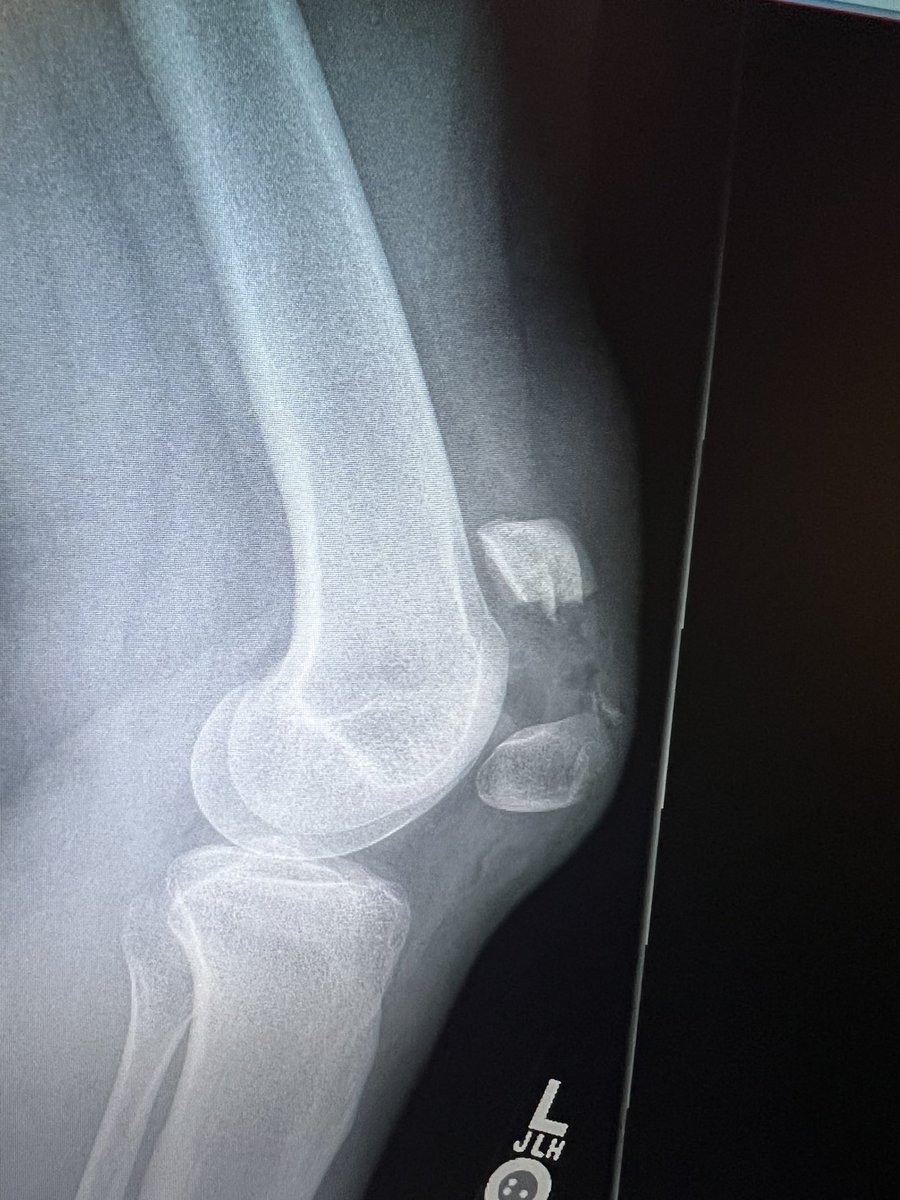

Meniscus root tears are important to recognize and address. Unfortunately, the natural history of a medial meniscus root tear can be seen in this patient when left untreated, with rapid progression of medial arthritis. #savethemeniscus #orthotwitter